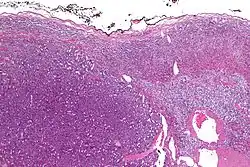

Micrograph of an adrenocortical carcinoma (left of image – dark blue) and the adrenal cortex it arose from (right-top of image – pink/light blue). Benign adrenal medulla is present (right-middle of image – gray/blue). H&E stain.